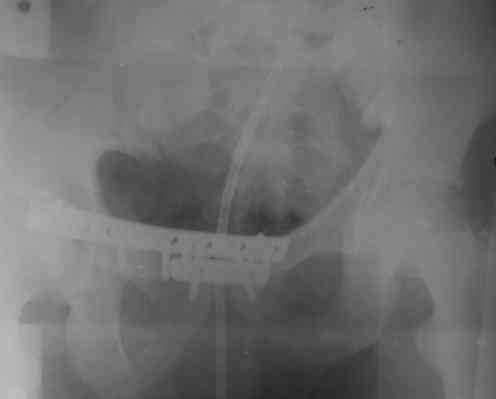

Уважаемые коллеги! На днях оперировал перелом таза месячной давности - разрыв симфиза, перелом обеих ветвей правой лонной кости, трансфораминальный перелом крестца слева. Представляю рентгенограммы с задержкой - технические причины.

Предоперационные рентген и КТ, в операционной - снимки после каждого фиксатора. Вертикальное смещение полностью устранить не удалось. В первую очередь за счет заднего полукольца. Хотя при компрессии на стержнях горизонтальное смещение было сантиметра 1,5. Т.е. крестец, на мой взгляд еще не сросся. От коллег хотел-бы услышать допустима-ли такая остаточная деформация?

Спасибо за обсуждение и ссылку. Во время операции, как я уже говорил, удалось дать приличную встречно-боковую компрессию. Неврологии у пациента не было и нет. Это и побудило сильно не усердствовать с репозицией трансфораминального перелома. На фоне фиксации спереди двумя пластинами, надеюсь, крестец срастется. Как будет возможность представлю контрольные КТ.